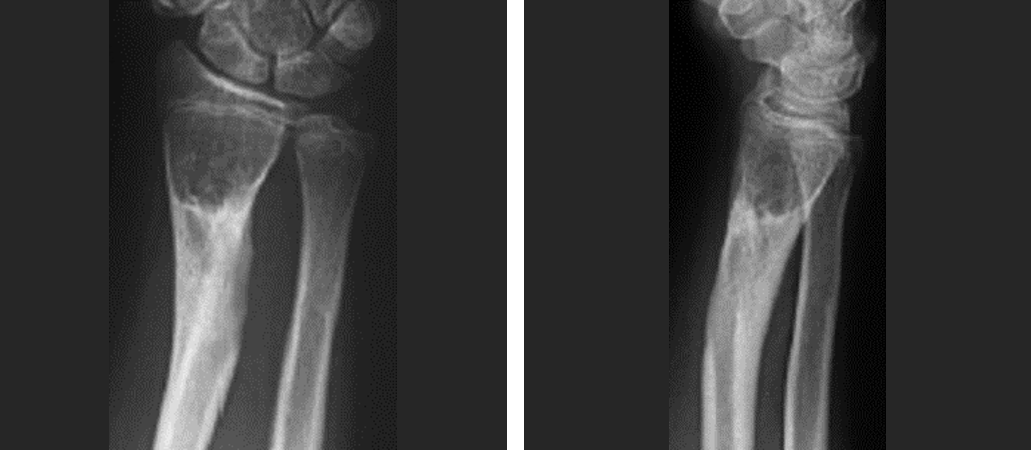

入院诊断:右前臂完全离断伤1.右尺,桡骨开放性骨折(ao:22-a3.2);2.

右肘关节开放性脱位,右桡骨远端开放性骨折 补充诊断:右第5掌骨基底